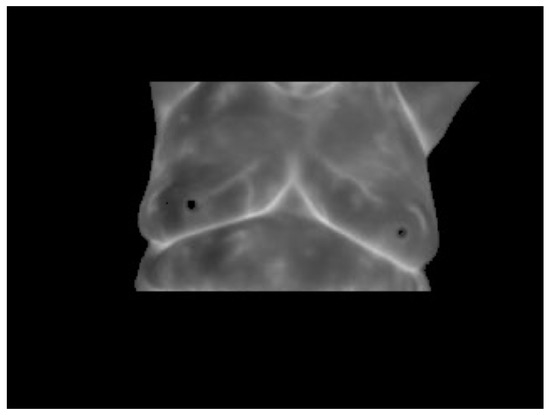

- Case 3, angiogenesis:The acquired histogram is shown in Figure 18a, and as in the previous cases, the pre-processing necessary to segment the breast regions can be followed step by step in Figure 18b–d. The segmented right and left breast are shown in Figure 18e,f, respectively. As in the previous case, a noticeable difference of temperatures can be seen in the thermogram in Figure 18a, with a lighter zone in the upper region of the left breast of the patient. This comparison is easier to achieve looking at Figure 18e,f.In Table 6 can be seen the estimation of the average difference of temperatures, which result in being 1.81 °C, with the left breast resulting in being hotter than the right breast, as expected. This is a clear indication of a detected problem, and now, the search for the hottest regions in the left breast is required. For this case, the difference of the maximum value and the standard deviation between the left and right sides is quite significant. In Figure 18, it is clear that one breast is lighter (or hotter) than the other.Watershed segmentation result can be seen in Figure 19. This time the hottest region is surrounding a cold zone and the resulting segmented shape can be associated with the one that blood vessels present resulting in an angiogenesis case. As mentioned earlier angiogenesis can be seen in early stages of breast cancer and subsequent medical exams are required, having the point of interest spotted in order to help the experts to correctly treat the patient.